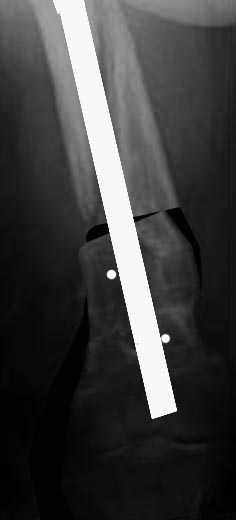

пациентка 58лет, ожирение III СТ., сахарный диабет 2 типа, 3 года назад БИОС бедра в г.Н-ске по поводу перелома в н\3, а теперь красота писаная!!!!! уважаемые коллеги! пациентка 58лет, ожирение III СТ., сахарный диабет 2 типа (субкомпенсированный), 3 года назад БИОС бедра в г.Н-ске по поводу перелома в н\3, нагрузка разрешена на ногу сразу, несмотря на вес, качество и метод остеосинтеза, а теперь красота писанная!! штифт убрали неделю назад с тех. трудностями, есть мнение выполнить, клиновидную остеостомию на уровне деформации, ретроградно с рассверливанием Expert с клинком и костной пластикой. Ваше мнение???С уважением.Керимов Артурцентр травматологии и ортопедии ГВКГ им.Н.Н.Бурденког.Москва

Не получилось послать снимки в нормальном качестве, но реально- каналы от удаленных винтов в дистальном фрагменте толщиной до 2.0см, выраженный остеопороз, "вальгус" на скиаграмме -25гр. Рекурвация- 20гр.